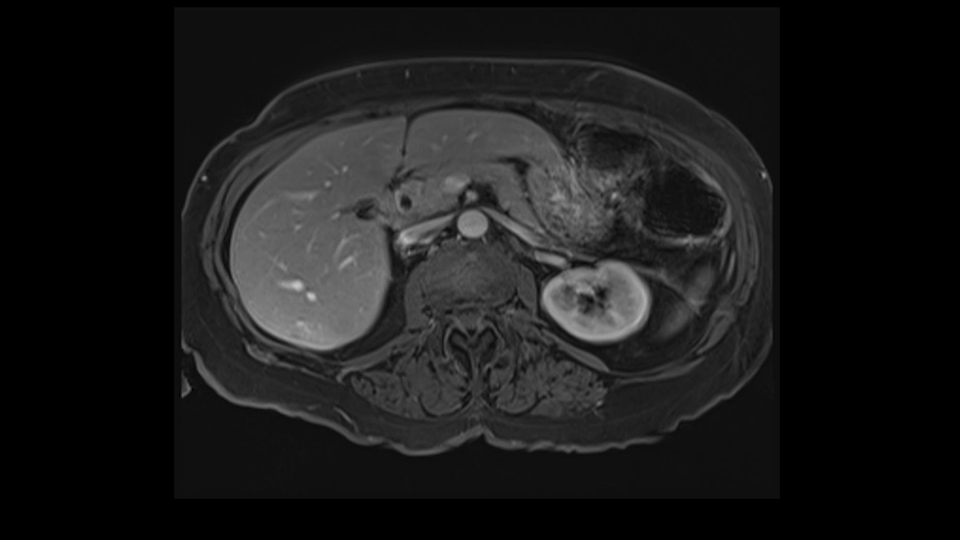

She underwent neo-adjuvant chemotherapy and then had a series of additional investigations and the one that I’m focusing on in more finer detail is an MRI with Primovist and I’ve had the benefit of looking at the report. The main issues are in Segments 5,6, and 7. Three small metastases that remain and the radiologist also comments on the lack of biliary dilatation which was present before; implying that the intrabiliary metastasis somewhere at the origin of the Segment 7 duct, has regressed or been adequately well treated with chemotherapy. That’s probably where the difficult decision making comes in the OR. So from an oncologic point of view, I would plan for a right hepatic lobectomy. The rationale would be that this would include the more peripheral Segment 5, 6, 7 metastases that are obvious but also would take care of the presumed Segment 7 intrabiliary metastasis that does not actually visualize on any of the scans but is assumed to be there with evidence of the duct dilatation which then resolved. One could argue whether we should preserve liver and ignore that duct dilatation that was there before but I think my own preference would be to resect the right lobe and that would certainly include any residual disease in that Segment 7 bile duct and moreover, coming back to do a completion right hepatic lobectomy would be difficult particularly around the porta where this metastasis is presumably still there and even if its quite small.

So when doing a major liver resection, obviously we would focus on a few issues. The first is hepatic parenchyma: is there adequate liver, residual liver and orientation and ratio of the right to left lobe here is pretty normal. It looks like its about 60:40 or 70:30, and because its only a right lobe, I probably wouldn’t do any volumes assuming she has normal liver function which I think she does. The only additional feature of interest is that she has received chemotherapy and one can see the effect of chemotherapy on the density of the liver but again, it doesn’t usually cause significant problems with a short course of neoadjuvant chemotherapy, or liver failure.

So I would then focus on the hepatic outflow because that’s the way we do the operation is by mobilizing the liver. So the vena cava looks quite normal. The right hepatic vein looks quite normal. There are no large additional outflow veins from the right lobe which would generate slowing down moments. The hepatic artery is unremarkable and is not usually an issue we can define the anatomy quite clearly at surgery.

So look at the MR from two points of view, firstly distribution of the lesions, secondly what kind of parenchyma would need to be resected to remove that disease and what kind of operation would we plan. And again so what we’re planning here would probably be a right hepatectomy. We know that there is plenty of disease-free left lobe. Segment 4 looks nice and clear. So a transection line coming down to about that kind of area would clear all of the disease. So that’s the kind of preoperative planning that we’d need to do.